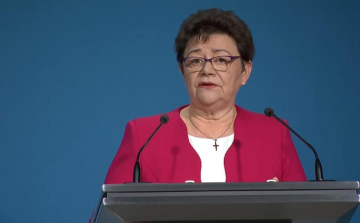

Müller Cecília: hétről hétre egyre több a fertőzött

A nagyvárosokban nőtt a koronavírus örökítőanyagának mennyisége a szennyvízben, de vidéken is stagnál és sehol sem csökkent - közölte az országos tisztifőorvos az M1 csatornán csütörtökön.